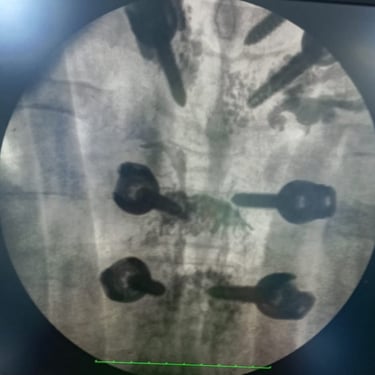

🧠 Fractura Vertebral Lumbar: Estabilización Segura con Fijación Transpedicular (FTP).

La fractura vertebral lumbar genera inestabilidad y dolor severo. La artrodesis con fijación transpedicular es una técnica quirúrgica eficaz que estabiliza la columna, previene desplazamientos vertebrales y mejora la recuperación funcional del paciente.